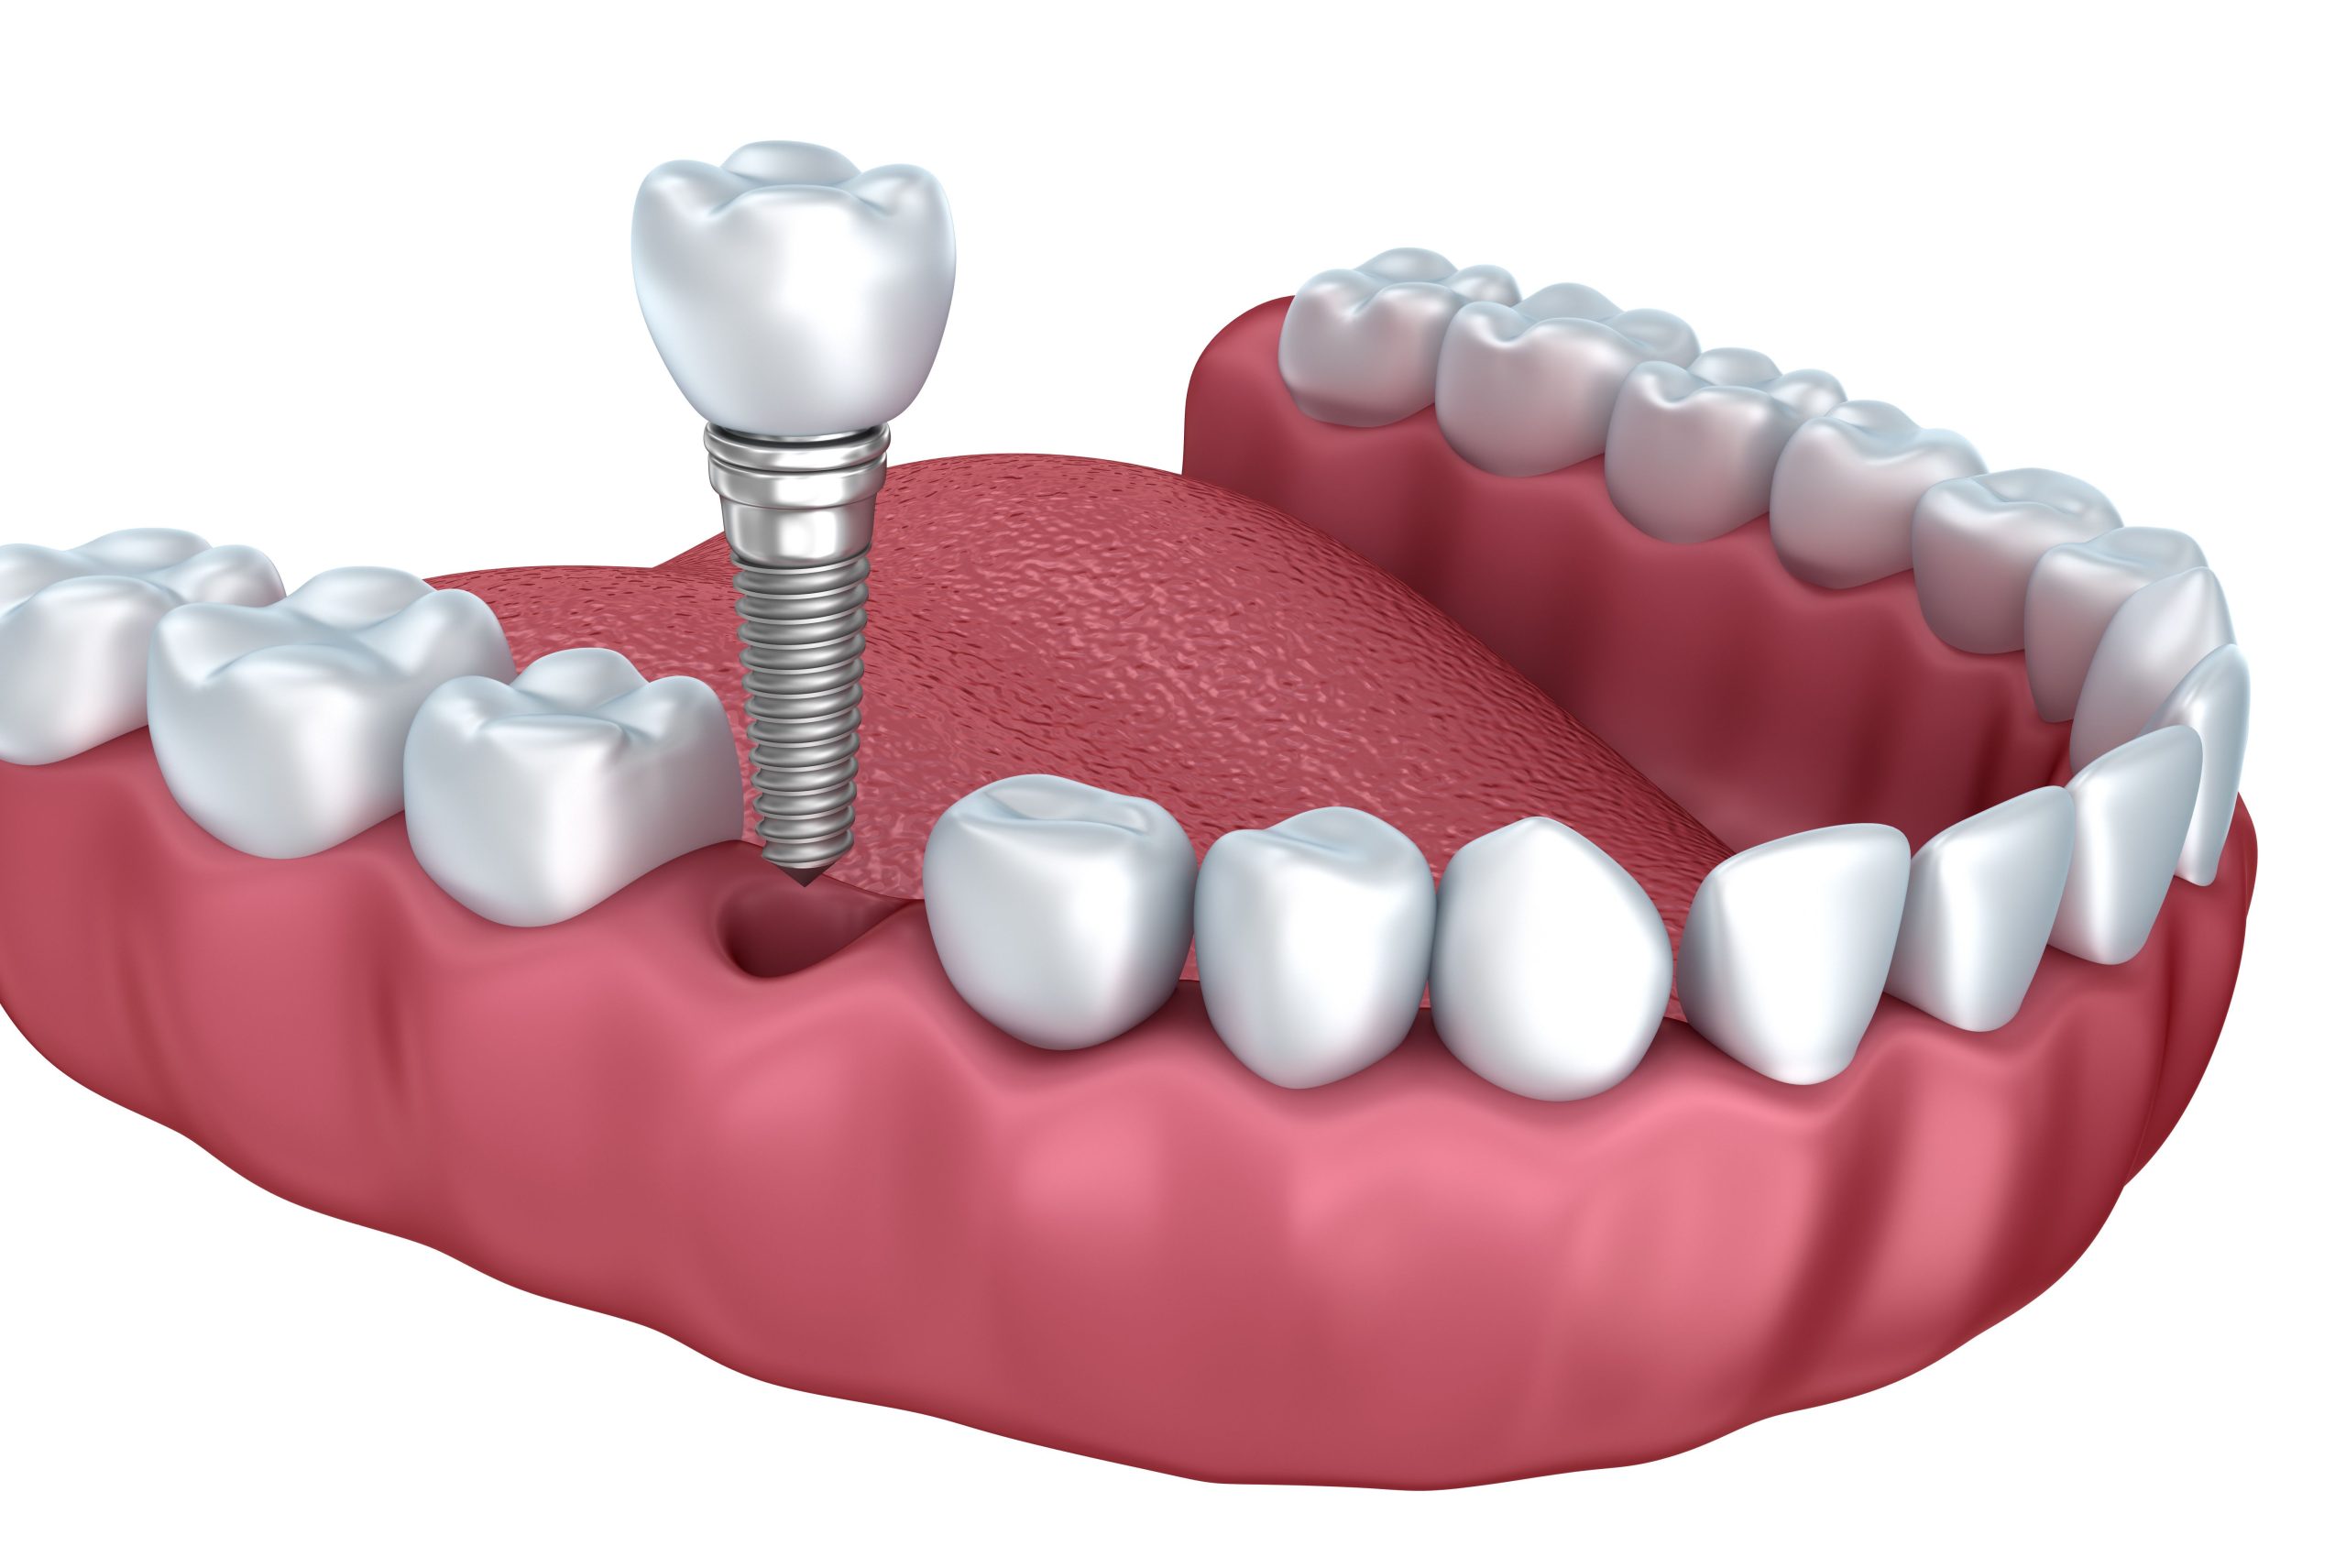

İmplant eksik dişlerin tedavisinde kullanılan ve çene kemiğinin içine yerleştirilen titanyumdan yapılmış vidalardır. Bu vidaların üzerine diş protezi yerleştirilir. İmplant tedavisinin diğer tedavilere avantajı komşu dişlere zarar vermiyor olmasıdır. İmplant diş kök görevi görür ve doğal diş gibi rahatlıkla yemek yiyebilir, konuşabilir ve gülebilirsiniz. Diş implantı cerrahisi, diş köklerini metal, vida benzeri direklerle değiştiren ve hasarlı veya eksik dişlerin yerine gerçek dişlere çok benzeyen ve işlev gören yapay dişlerdir.

İmplant işlemi öncesinde detaylı muayene ve röntgen gereklidir. Çene kemiklerinin ve kalan dişlerin ölçüsü alınır. Dental implantların yerleştirilmesi için iki seçenek vardır. Tek aşamalı işlemde implant yerleştirildikten sonra geçici başlık takılır. İki aşamalı işlemde ise dental implant takıldıktan sonra üzeri diş eti ile kapatılır ve iyileşmeye bırakılır. Protez başlıklar daha sonra takılır. Her iki durumda da geçici bir köprü yerleştirilir ve 3 ay iyileşme süreci beklenir. Bazen dental implantların üzerine yeni yapılan dişler hemen takılabilir.